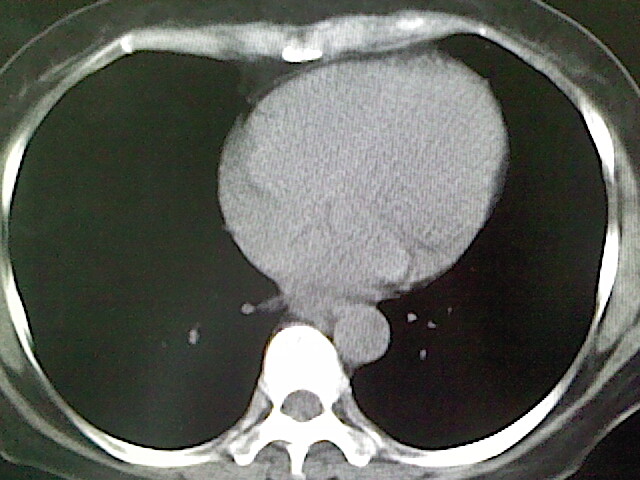

女,52岁,咳嗽,咳痰多日

左下肺陈旧纤维索条!

左肺舌段炎性改变

我见过几例,为炎症后纤维条索

慢性炎症后改变

考虑慢性炎性病灶粘连牵拉改变。

左肺舌叶纤维锁条病变。

左肺上叶下舌段炎症并局部胸膜反应。

左肺舌叶纤维索条影。

左肺舌叶段陈旧性病变

左肺舌段炎性反应。片子的质量太不好了。

左肺舌段炎性

炎性改变

左肺舌叶纤维索条影